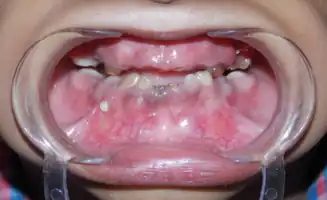

| Shows the severe underbite pattern that is a common development pattern in individuals with Tricho Dento Osseous Syndrome | |

In the oral cavity 100% of people diagnosed with TDO have taurodontism which is characterized by vertically enlarged pulp chambers at the expense of the roots of the teeth; the floor of the pulp chamber and furcation is moved apically down.[1] This is due to the failure of the Hertwig epithelial root sheath which maps the shape of the forming tooth roots during active differentiation. Amelogenesis imperfecta, an abnormal formation of the enamel or external layer of the crown of the tooth, may also be present where the tooth enamel may be thin or absent. There are several clinical subsets of amelogenesis imperfecta, but common to TDO is the hypoplastic-hypomaturation subtype;[3] the hypomaturation-hypoplastic is less common in individuals with TDO. The difference between the 2 dominant subtypes is the changes seen in the enamel matrix, and the phenotypic type that predominates. The hypoplastic-hypomaturation type of amelogenesis imperfecta with TDO occurs where the tooth enamel depicts a generalized pitted pattern, with open contacts between the teeth as well as an open bite. A smaller number of cases are of the hypomaturation-hypoplastic case type, in which the enamel structure is softer due to the under maturation of ameloblasts during development. Mandibular prognathism also called a severe underbite, is also a prominent feature in TDO. Prognathism defects are diagnosed based the level of severity that this condition interferes with being able to chew or speak properly.